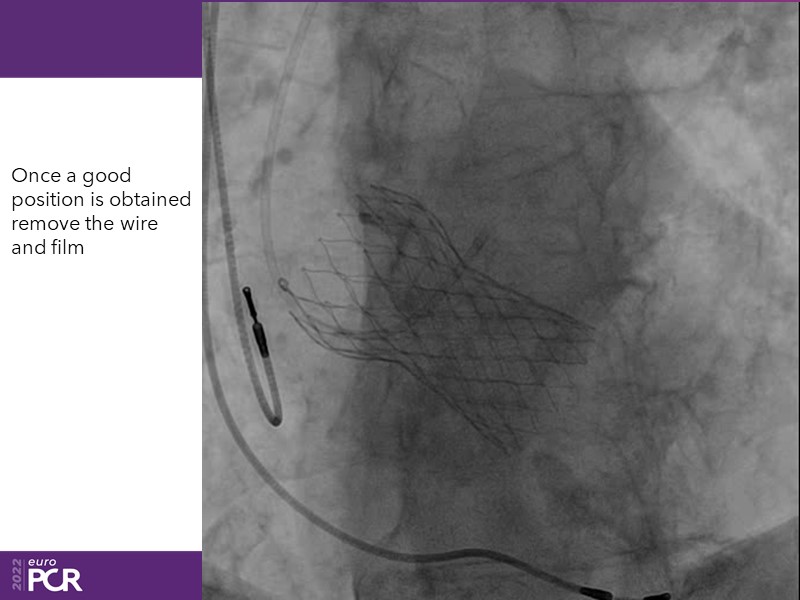

Consult this session to learn how to contribute to streamlined pre- and post-TAVI patient pathways, to discover updates on the optimised TAVI procedure and appreciate the variances in different valve designs and the long-term patient outcomes, as well as to discuss the right time of PCI in TAVI patients (steps on the procedure).

- To discuss the right time of PCI in TAVI patients (steps on the procedure)